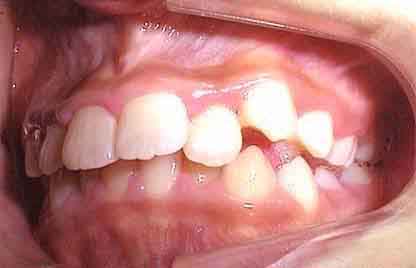

初診の状態